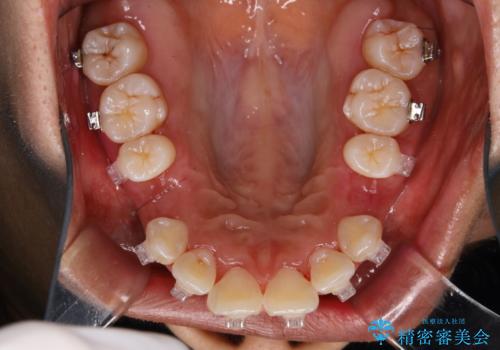

- ワイヤー矯正中の患者様です。職場で口臭を指摘されたとのことでした。

ワイヤー矯正中はブラッシングが難しくなるため、磨き残しが多くなることがあります。適切な道具を使って、適切なブラッシング方法を習得することで、磨き残しを減らすことができます。

また、矯正で歯の移動があると今までなかったところに隙間が出てきたり、ガタつきが解消されてきたりすることで、お口の中の環境が変わります。